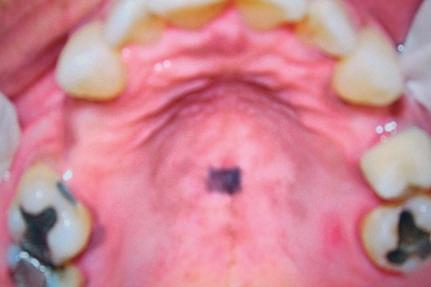

Manchas

São alterações de cor da mucosa ou pele, uniformes e sem relevo, podendo variar desde colorações mais claras, brancas até as mais enegrecidas, amarronzadas e arroxeadas, dependendo do tipo de pigmento. Não apresentam tamanho definido, podem ser puntiformes ou atingirem alguns centímetros (Fig. 1-1).

Exemplos: melânicas (pigmentos endógenos [Fig. 1-2], e exógenos [Fig. 1-3]), hemáticas (vasculares e hemorrágicas [Fig. 1-4]).

Vale lembrar que, classicamente, para as manchas secundárias devemos denominá-las de mácula, como por exemplo as manchas melânicas (Fig. 1-5) e eritematosas após trauma.